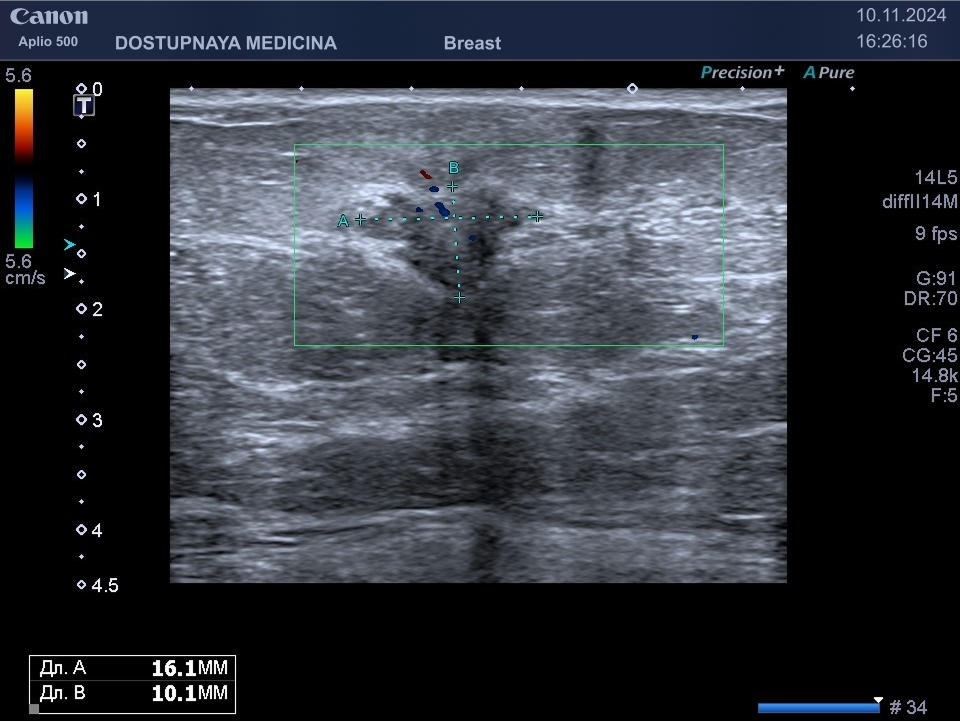

При ультразвуковом исследовании в кисте может быть визуализирован папиллярный компонент с кровотоком в режиме ЦДК. Так могут выглядеть цистаденопапилломы, которые считаются аблигатным предраком.